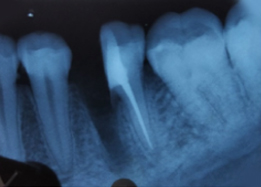

Radiograph with Prosthesis (8 Months)